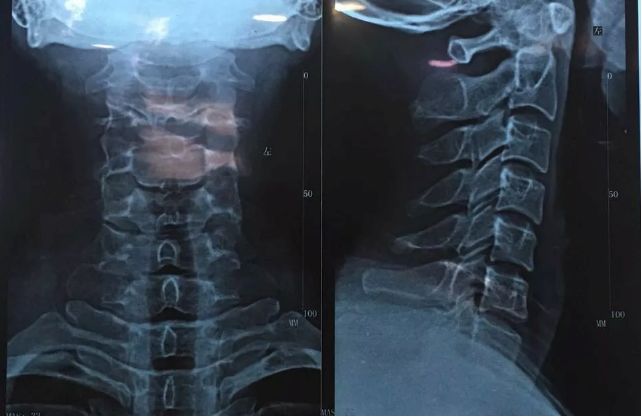

在这个低头族越来越多的时代,颈椎病成了常见病、多发病,且发病年龄日益年轻化。

颈部即我们俗称的“脖子”,它是身体最细的部位,却是连接头颅与躯干的“生命线”。万病之源,起于颈椎,颈椎一旦发生病变,不仅会造成颈部僵痛疼痛,引起多种症状,还会引发各种严重的并发症!

患上颈椎病怎么治?

颈椎病的治疗一般建议保守治疗,只有严重的脊髓型颈椎病及经过保守治疗无效果或治疗后反复发作的患者则需要手术治疗。